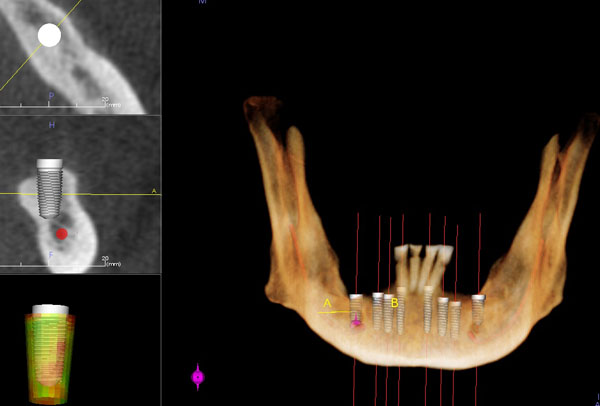

Dental CT Scan

Dental CT scan that involves 3D view of entire oral maxillofacial region (Galileos Compact, 3D Scan machine from Sirona) will also be taken of your teeth. A three-dimensional model of the mouth is a supreme assistance for implantology when planning tooth implants, but is correspondently popular for other fields of dentistry.

The 3D simulation permits doctors to:

• CT scans are essential for the accurate placement of dental implants.